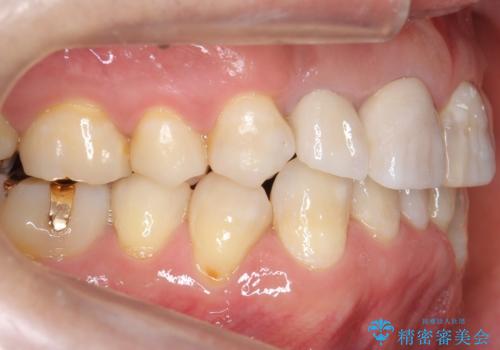

仕上がりに限界はありましたが、比較的短期間で歯並びが整いセラミック治療を行うことができ、患者様に「治療して良かった」とご満足頂けました。

左上1の歯の表面にもともと凹凸とグラデーションがあり、気になるようならセラミックでかぶせるのも一つだと提案しましたがご希望されなかったため、その表面性状を再現して右上1のセラミッククラウンを作製しています。

右上21:ジルコニアクラウン スペシャル

左上6:ジルコニアクラウン スタンダード

左上7:e-max press セラミックインレー